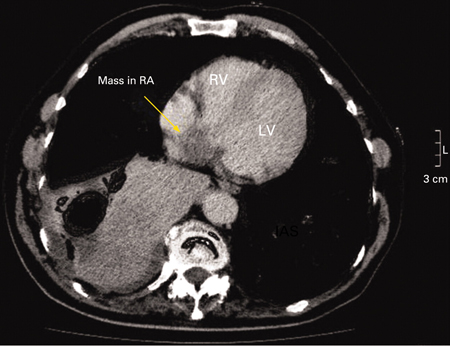

[Figure caption and citation for the preceding image starts]: Chest CT demonstrating a mass in the right atrium (RA) subsequently confirmed to be an atrial myxoma. RV = right ventricle, LV = left ventricleA Yavari, H El-Mahy, ET McWilliams. BMJ Case Reports 2009; doi:10.1136/bcr.10.2008.1031 [Citation ends].